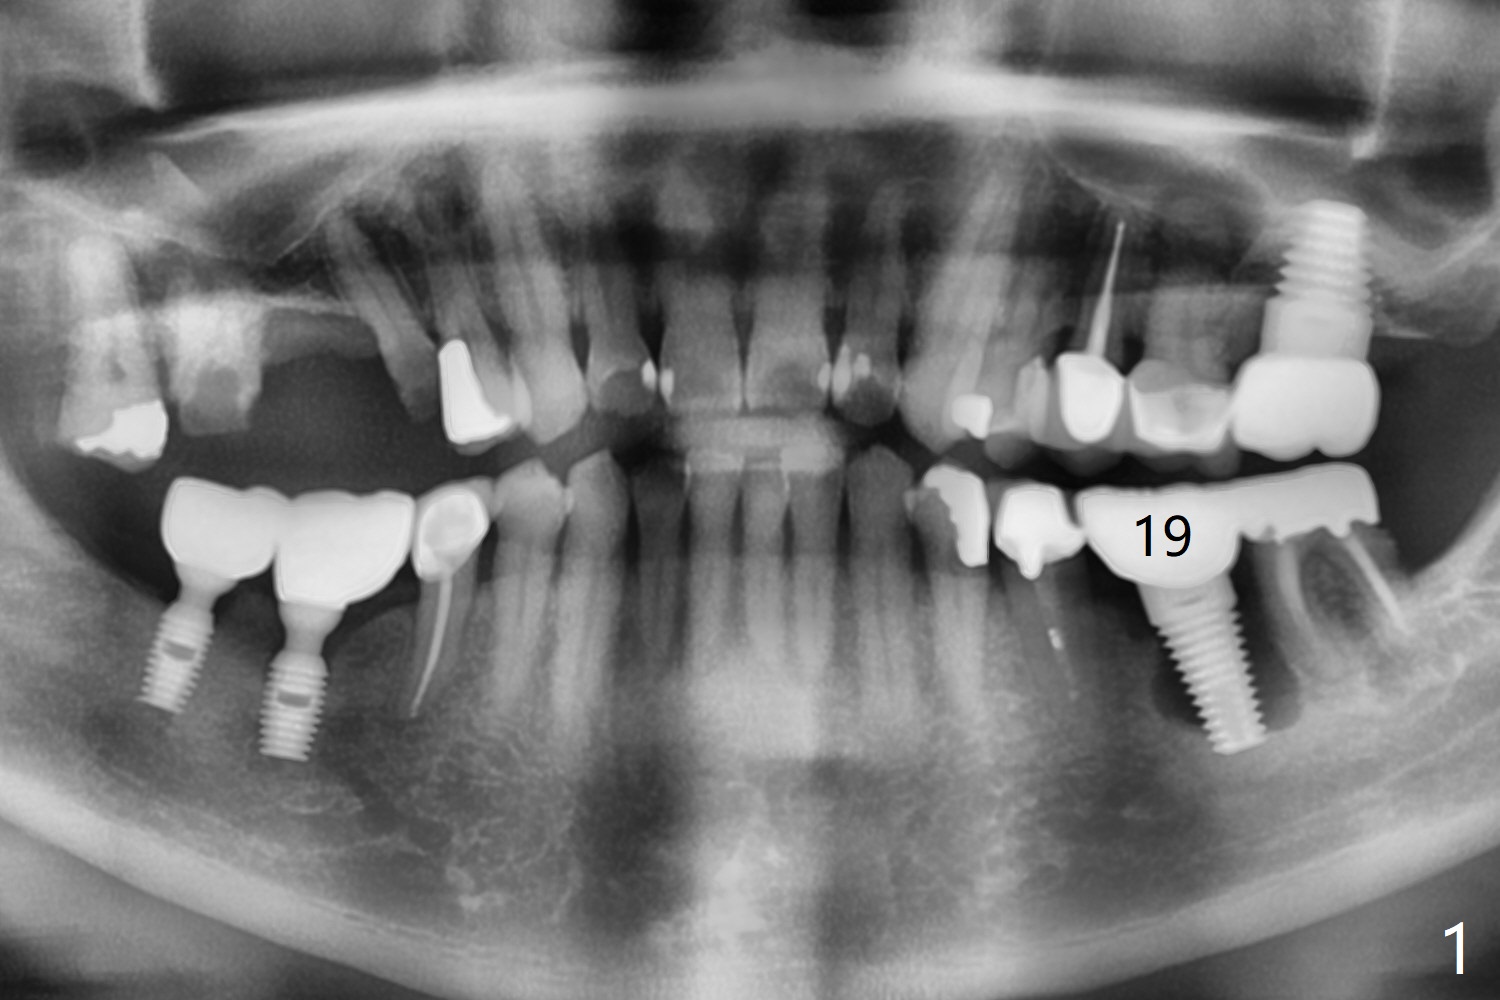

Augma Post Implant Removal I

A 66-year-old man returns with chief complaint of chewing pain lower left. There is severe bone loss around the implant at #19 (Fig.1,2). Section the crown, remove the 6 mm abutment (no cement) and 7 mm implant. After debridement and copious irrigation, place Augma, press, place Collagen plug and 4-0 PGA. Take PA and place acrylic or periodontal dressing if needed. Is the defect too large for 1 cc Bond Apatite? Place allograft in the bottom of the defect before Bond Apatite?